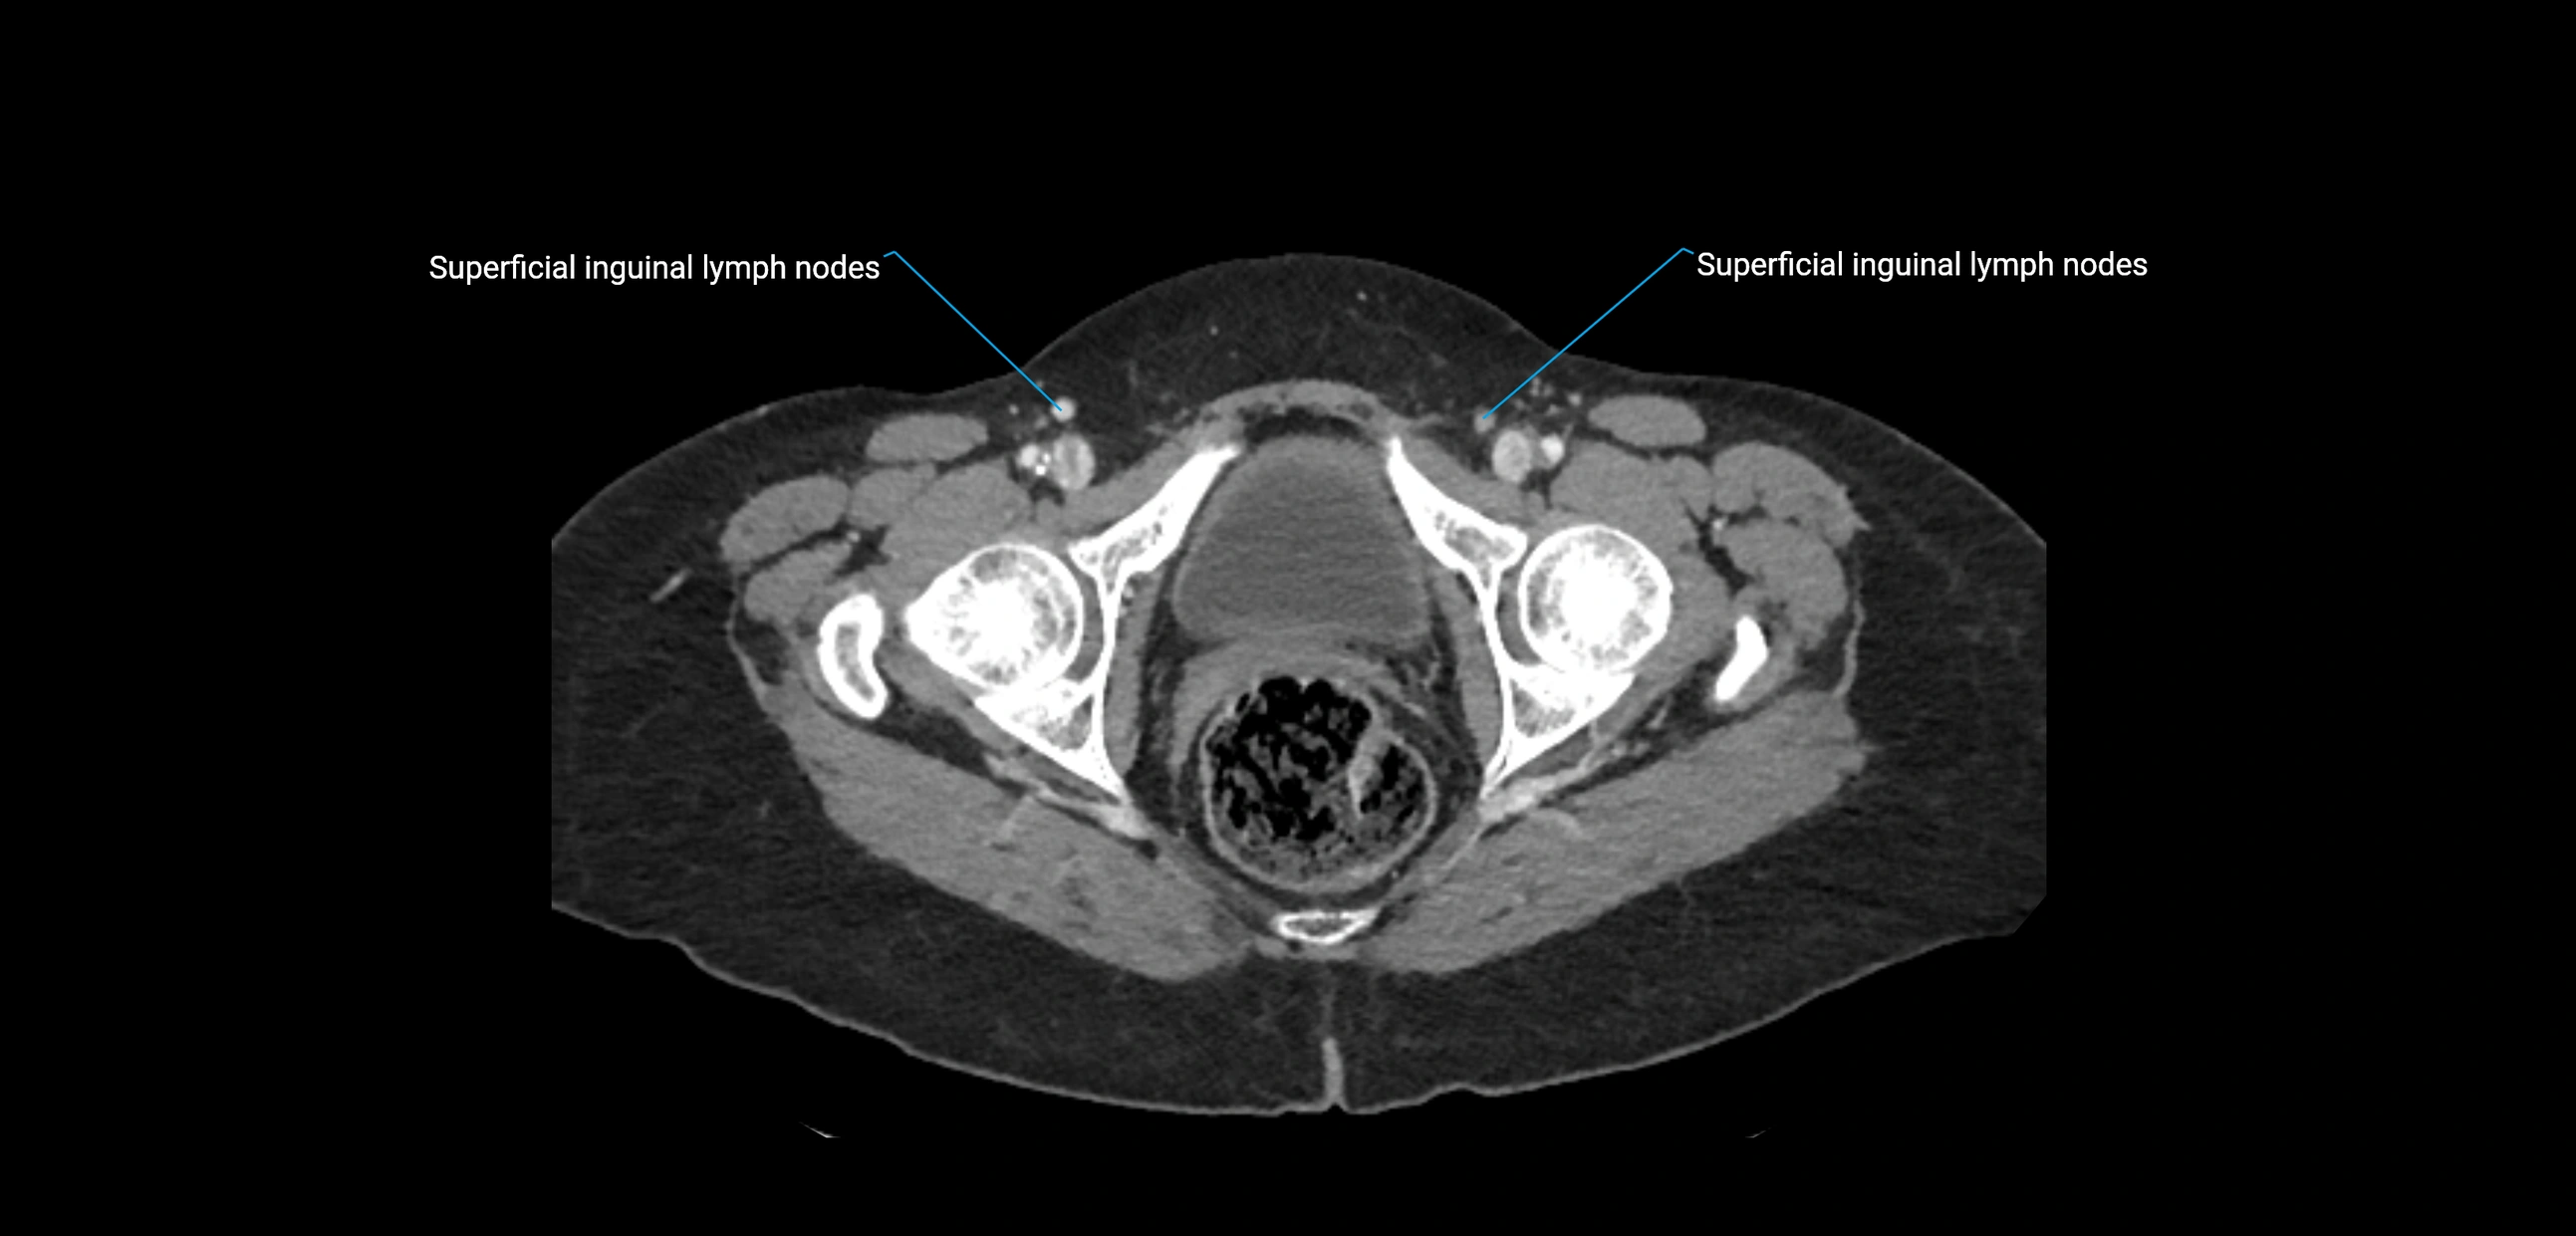

CT Appearance

CT Pre-Contrast:

• Nodes appear as soft-tissue density nodules adjacent to the aorta and IVC

• Calcification may be seen in chronic infections (e.g., tuberculosis)

CT Post-Contrast:

• Normal nodes enhance homogeneously

• Malignant nodes may show heterogeneous enhancement, central necrosis, or conglomerate formation

• Size >1 cm short axis is suspicious, though morphology and distribution are equally important

CT image

image